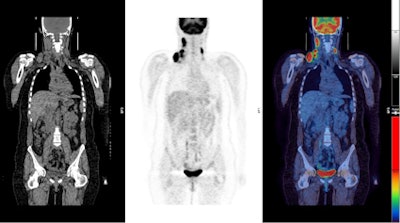

PET/CT images show a Hodgkin's lymphoma patient with a negative PET scan after chemotherapy. There is high uptake in lymph nodes on both sides of the neck prior to treatment (above), which resolved after chemotherapy (below). Physiological uptake is also seen in the heart and bladder. Images courtesy of Dr. Sally Barrington, reader in nuclear medicine, PET Imaging Centre at St Thomas' Hospital in London.Hodgkin's lymphoma occurrence